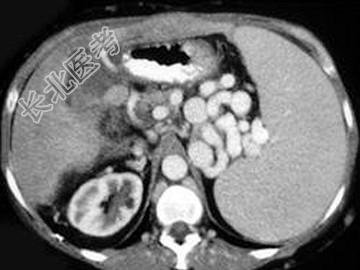

- 单项选择题男,50岁, 患乙肝多年,现腹胀, 右上腹痛,消化不良, 消瘦、乏力、贫血、黄疸,血清转氨酶升高, 白蛋白/球蛋白比值倒置。CT检查如下图,最可能的诊断是 ( )

A、肝硬化、肝癌

B、肝硬化、腹膜后淋巴结肿大

C、肝硬化、肝癌、腹膜后淋巴结肿大

D、肝硬化、门脉高压、脾大

E、肝硬化、脾大